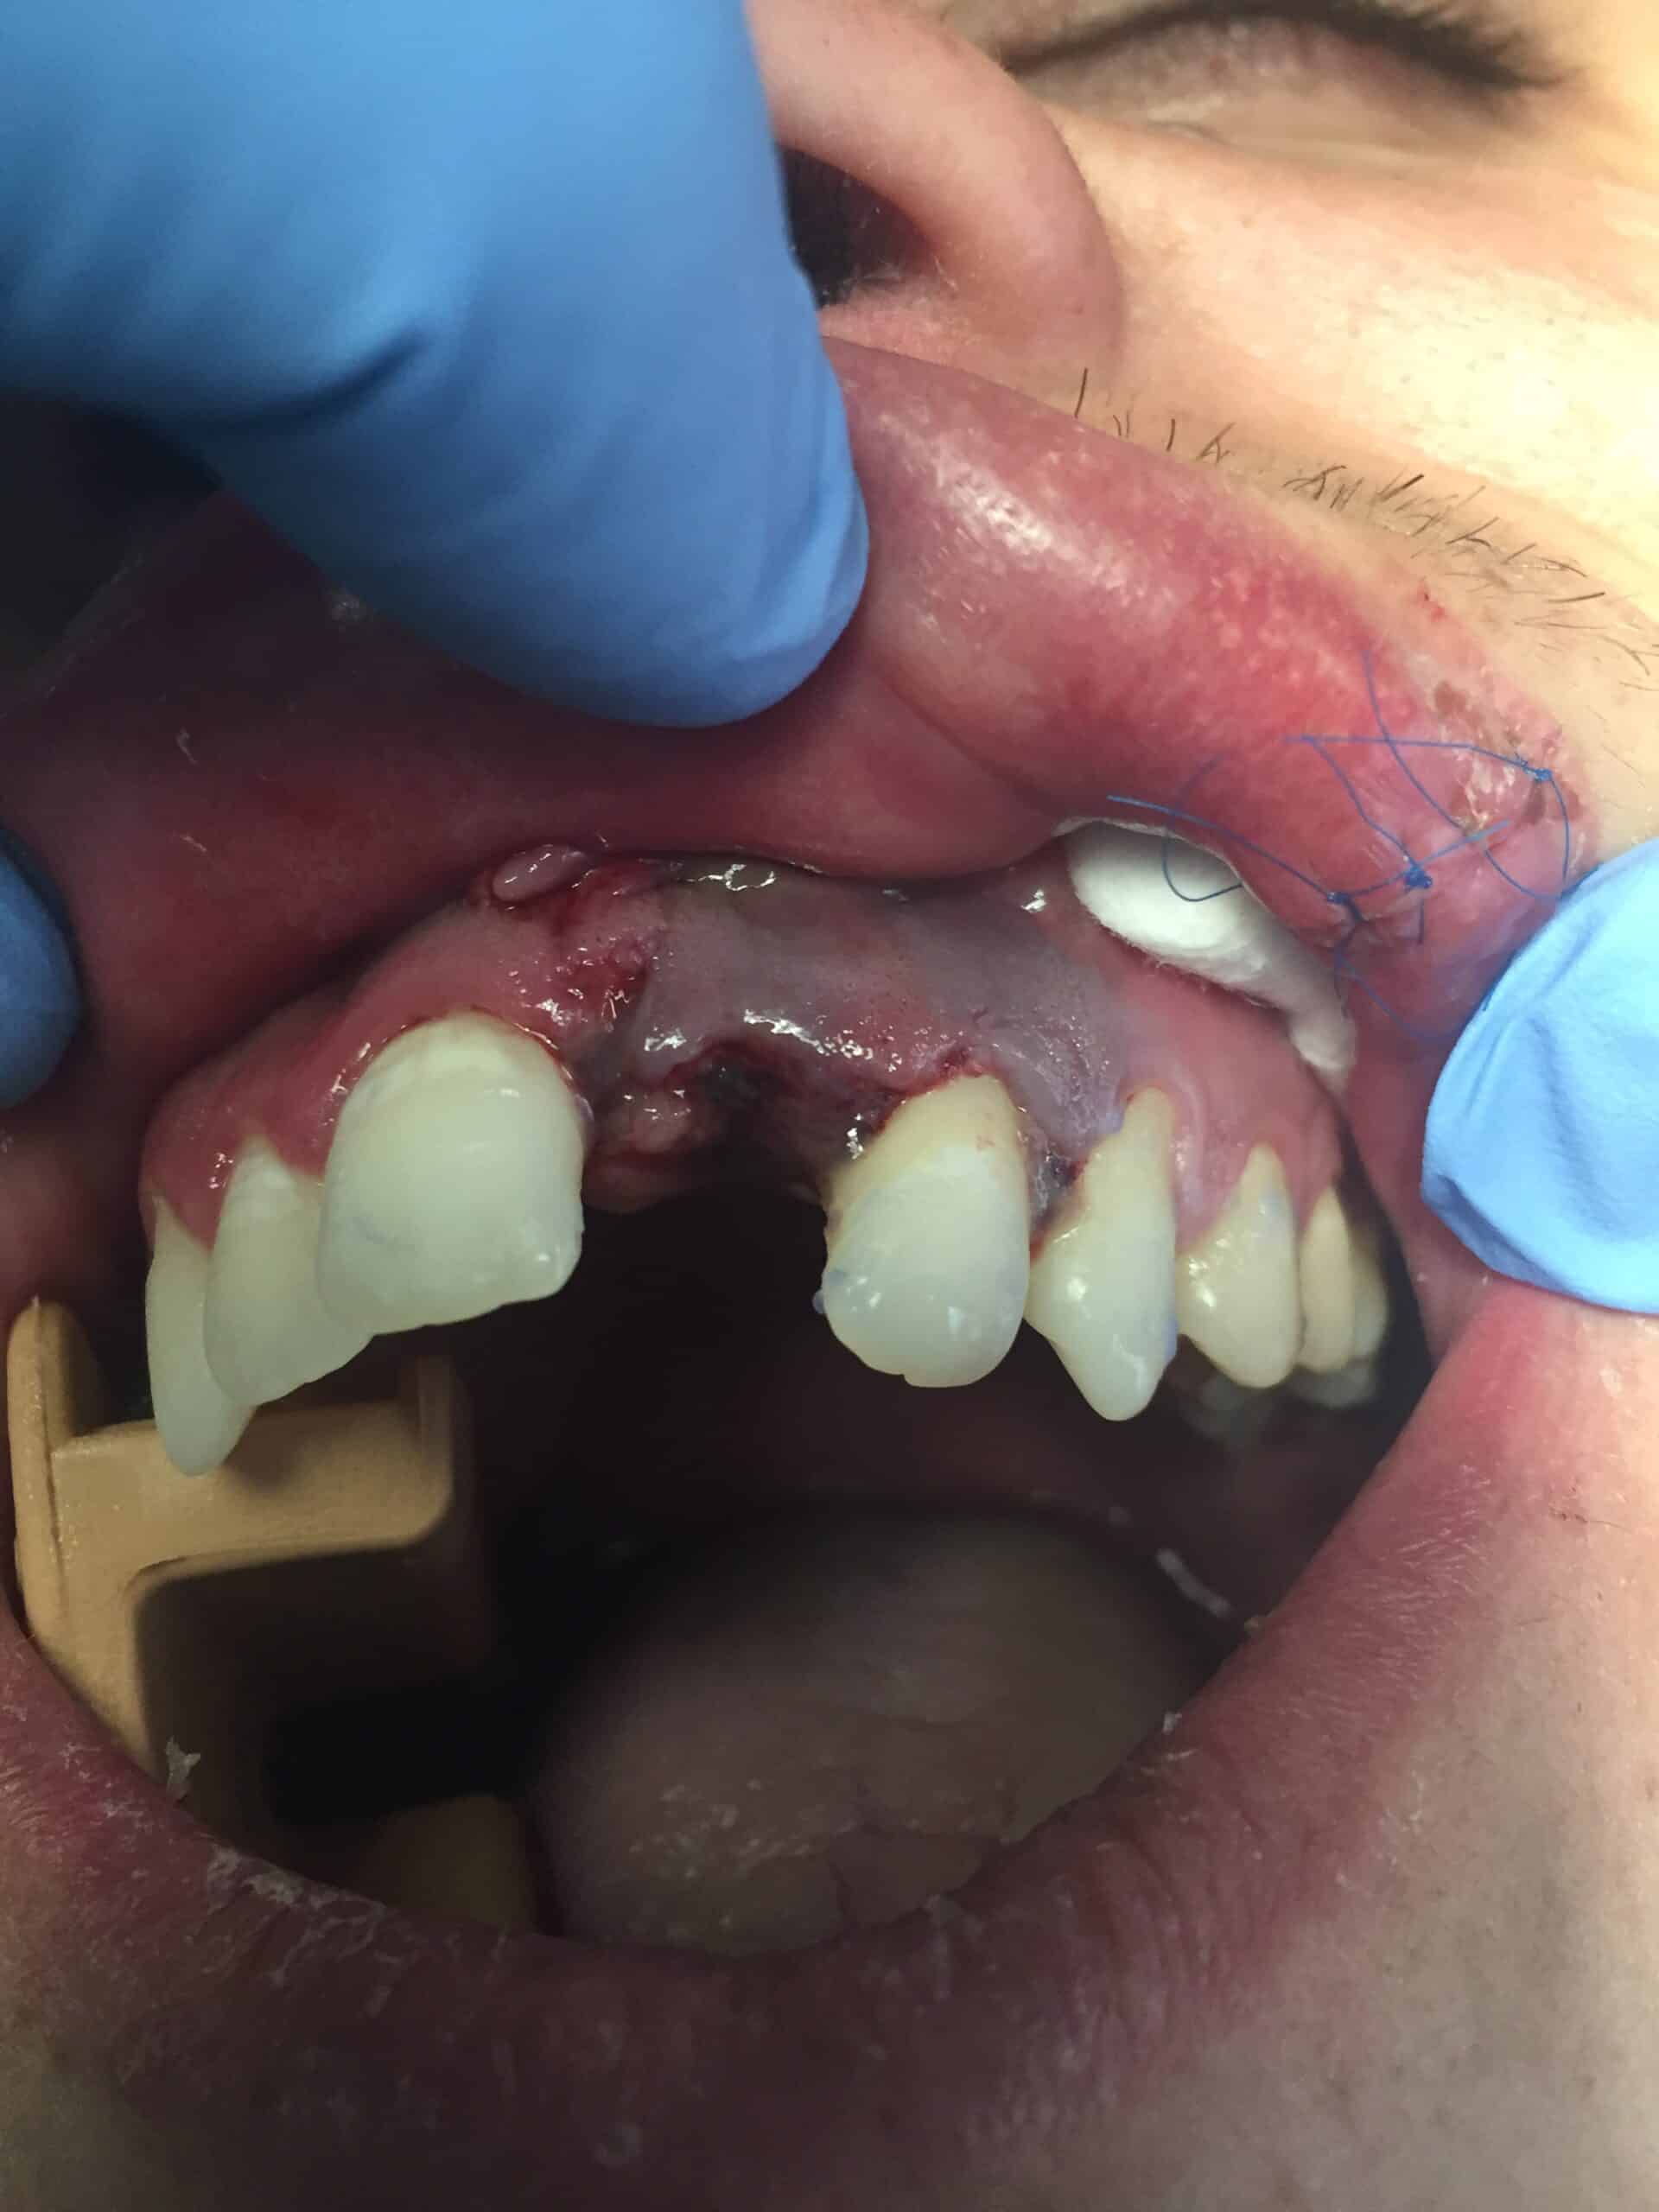

Avulsion